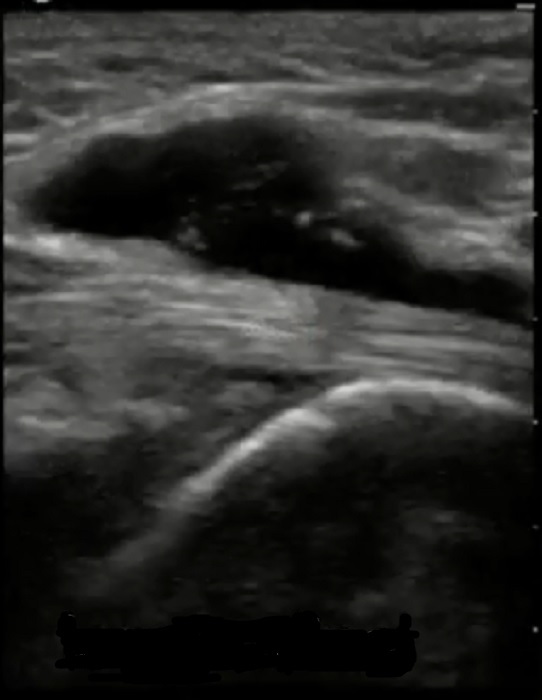

Bild: Fuß und Sprunggelenk, fehlgebildeter Flexor hallucis longus, longitudinal